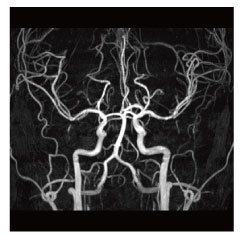

MRI(Magnetic Resonance Imaging:磁気共鳴画像診断装置)検査は、強力な磁石でできた円筒状の機械に入り、磁気や電波の力を利用して体の断面や血管を撮影する検査です。

当院のMRI画像集